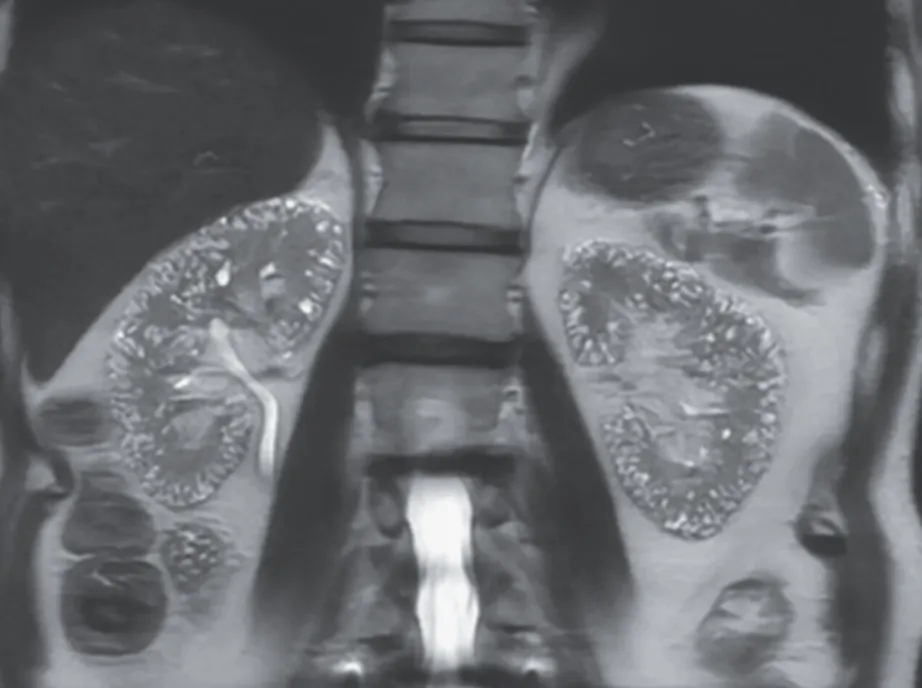

Uma causa incomum de hematúria glomerular intermitente!

Hematúria pós infecção, caso clínicos para auxiliar no entendimento de causas glomerulares comuns e raras...